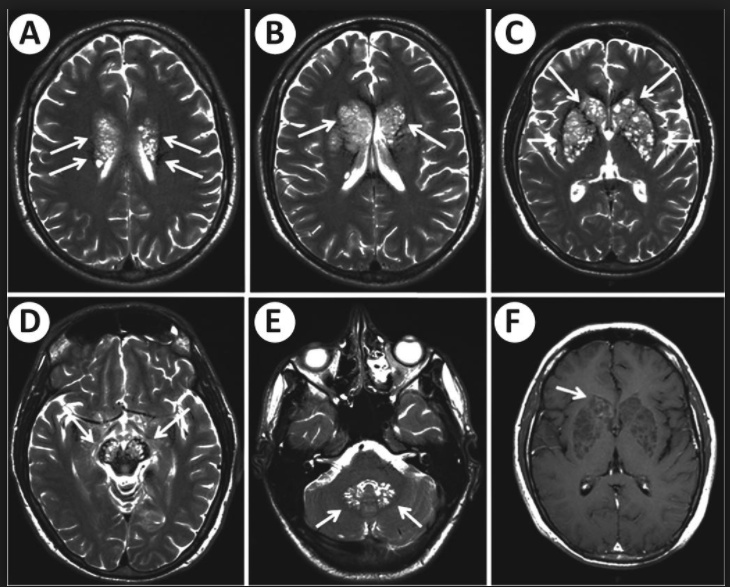

soap bubbles on head: Causes "soap bubble" lesions in gray matter

soap bubbles on lung: Diagnose with a microscopic exam of bronchopulmonary washing

red and silver stripes: Diagnosis of pulmonary Crypto can be aided by mucicarmine or methenamine silver stain